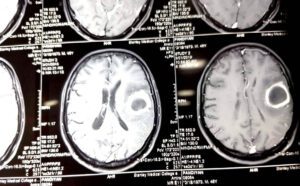

மூளையில் கட்டி: தலைவலிகளிலேயே மிகவும் அபாயகரமானது மூளையில் கட்டிகளால் வரக்கூடிய தலைவலியே ஆகும். ஏனென்றால் ஆரம்ப காலக் கட்டத்தில் மற்ற சாதாரண தலைவலி மாத்திரைகளுக்கே கட்டுப்படும். அதனால் மருத்துவப் பயனாளிகள் அலட்சியமாக இருப்பதற்கு வாய்ப்பு அதிகம். இவ்வகையான தலைவலிகளுக்கு சில அறிகுறிகள் உள்ளன.

நெற்றிப்பொட்டில் வலி: காலையில் எழுந்தவுடன் நெற்றிப் பொட்டில் அதிக வலி இருக்கும். வாந்தி வரும். வாந்தி எடுத்தவுடன் தலைவலி குறையும். தலைவலி மிகவும் அதிகமாகும் தருணத்தில் கண் பார்வை மங்குவதற்கான வாய்ப்புண்டு. இம்மாதிரியான மருத்துவப் பயனாளிகளுக்கு கூடுதலாக கீழ்க்கண்ட சில அறிகுறிகள் இருக்கலாம்.

1. வலிப்பு நோய். 2.கண்பார்வை மங்குதல். 3.காது சரியாக கேட்காமல் இருப்பது. 4. நடந்தால் தடுமாற்றம் ஏற்படுவது. 5. கை, கால்களில் பலம் குறைவாக இருப்பது. சொரணை குறைவாக இருப்பது போன்ற அறிகுறிகள் இருக்கலாம்.

இந்த மருத்துவப் பயனாளிகளை அவசரமாக சி.டி. ஸ்கேன் எடுத்து வைத்தியம் செய்ய வேண்டும்.